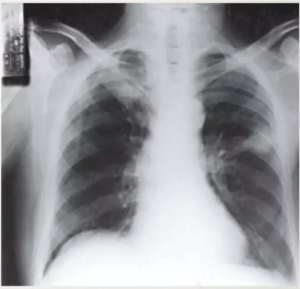

• POST-PRIMARY TUBERCULOSIS/REACTIVATION TUBERCULOSIS

• Predilection for upper lobes

• Lack of lymphadenopathy

• Propensity for cavitation

• ⁠The predilection for the upper lobes is thought to be due to decreased lymph flow in the upper regions of the lung.

• An alternative explanation is the presence of higher oxygen tension in that region.

• ⁠ ⁠Xray showing cavitatory consolidation in right upper lung zone and multiple ill-defined nodules in both lungs

CAVITATION AND TREE IN BUD SIGN IS INDICATIVE OF AN ACTIVE DISEASE PROCESS AND USUALLY HEALS S A LINEAR OR FIBROTIC LESION.